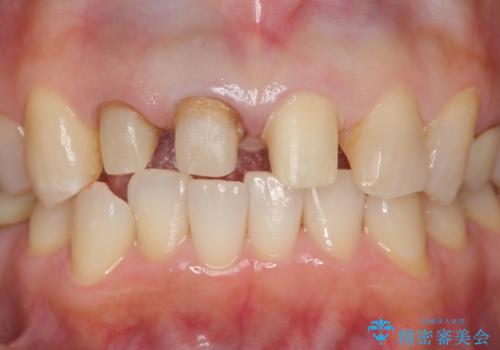

- 前歯のすき間を気にして来院。

右上2本を以前セラミックにしたが、前歯のすき間が広がってきてしまったとのこと。

右上の前歯のみの被せなおしですと、右上の前歯が反対側に比べて極端に大きくなってしまうことを説明し、左上の前歯も併せてセラミックにすることにしました。

右上の前歯二本、左上の前歯1本をセラミックにし、正中の前歯を2本連結しました。

連結しなくても、ナイトガード使用で防止できると説明しましたが、手間をかけずに二度と広がらない方がいいとのことで連結を強くご希望でした。

連結のデメリットはフロスができなくなってしまうことになるため、歯間ブラシを使用していただいてメンテナンスしていただくことになります。7

また、見た目の歯と歯の分離感も、連結しない方が表現することが可能です。